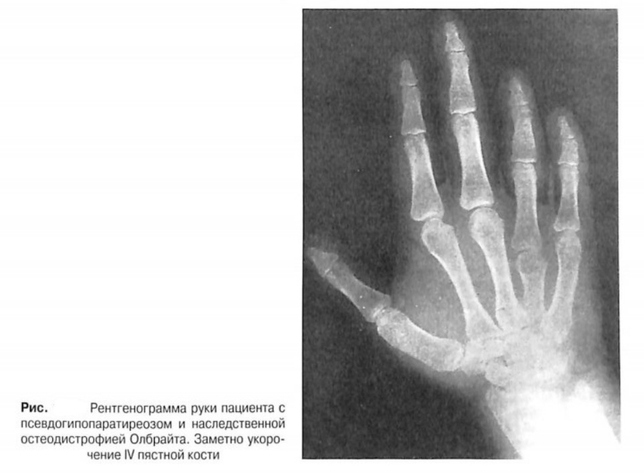

Псевдогипопаратиреоз

Идиопатические наследственные формы резистентности к ПТГ называют псевдогипопаратиреозом (ПГП). Существует два основных типа ПГП:

1 тип, который характеризуется нарушением цАМФ и фосфатурического ответов на ПТГ,

2 тип, при котором ответ цАМФ и ПТГ сохраняется, а фосфатурический ответ - нет.

Впервые ПГП был описан Олбрайт в 1942 году, у пациентов присутствовали гипокальциемия и гиперфосфатемия, а также ряд признаков, которые сегодня называют наследственной остеодистрофией Олбрайта (НОО). К этим признакам относятся низкий рост, округлое лицо, укорочение IV и других пястных костей, ожирение и подкожные кальцификации.